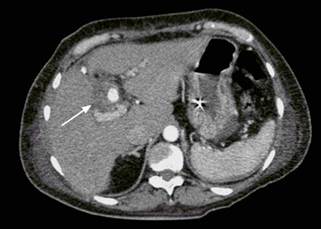

Posterior a esto, se programó para colecistectomía abierta con exploración de vías biliares. En el procedimiento se evidenció la vesícula con paredes engrosadas, con síndrome de Mirizzi grado IV; se realizó la extracción de un gran cálculo de la vía biliar mediante el uso de pinzas de Randall, se realizó un lavado exhaustivo de la vía biliar y se decidió dejar un tubo en T. Presentó una evolución tórpida durante el posoperatorio temprano, por lo que al tercer día se decidió realizar una tomografía axial computarizada (TAC) de abdomen en la que se evidenció una colección perihepática anterior, la cual es drenada de manera percutánea con éxito; y se obtuvo salida de material bilioso. A los 3 días del drenaje presentó abdomen agudo, por lo que requirió una reintervención, en la que se evidenció bilioperitoneo y tubo en T desalojado; se evacuó el líquido peritoneal y se realizó una coledocorrafia con parche de epiplón. Se trasladó a la unidad de cuidados intensivos (UCI) con soporte ventilatorio y vasopresor; allí se documentó la aparición de Klebsiella pneumoniae y Enterobacter cloacae en el líquido peritoneal, que fueron manejados con antibiótico dirigido. En los días siguientes presentó hematemesis y caída de la hemoglobina, por lo que fue llevada a endoscopia, en la que se evidenció un sangrado a través de la papila; por tanto, se realizó el manejo con escleroterapia, sin lograr control del sangrado; entonces se realizó una angiotomografía de abdomen en la que se encontró un pseudoaneurisma de la arteria hepática derecha con comunicación a la vía biliar (Figura 2).

Figura 2 Angiotomografía de abdomen. Pseudoaneurisma de la arteria hepática derecha. Área hipodensa que rodea el vaso en contacto con la vía biliar (flecha).